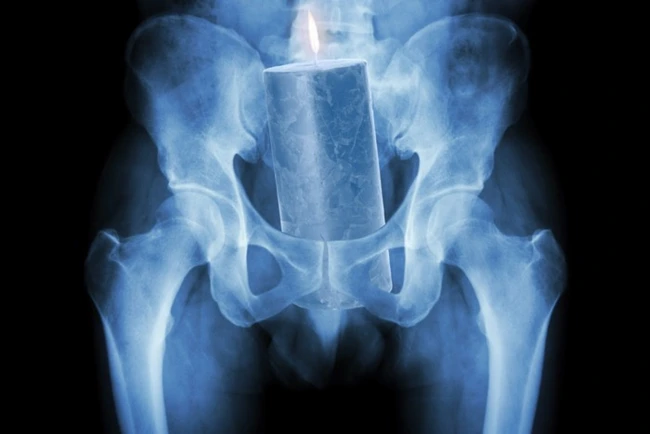

Un american în vârstă de 50 de ani a ajuns la urgenţe spunând că are o lumânare în rect, relatează The Cut.  Iniţial, medicii au crezut că bărbatul glumeşte, dar sub presiunea durerii, acesta a început să le descrie lumânarea. Obiectul s-a dovedit a fi de mare dimensiune, fiind aproape imposibil de crezut că introducerea acestuia în rect chiar a fost posibilă. Victima a fost, în cele din urmă, operată pentru a putea scăpa de obiectul străin.